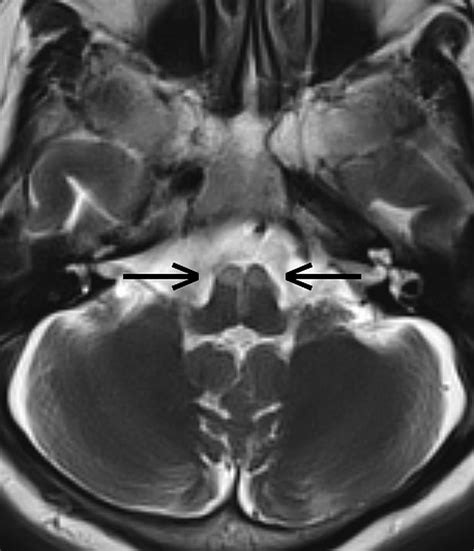

Learn about Lateral Medullary Stroke, also known as Wallenberg syndrome. This guide covers essential neurological symptoms, underlying causes, and diagnostic approaches for this brainstem infarction. Understand the impact of posterior inferior cerebellar artery (PICA) blockage and explore modern recovery strategies to improve patient outcomes and long-term prognosis after this complex stroke event.

TitleA case of bilateral stroke of the medulla oblongata | Journal of Neurology, Neurosurgery ...